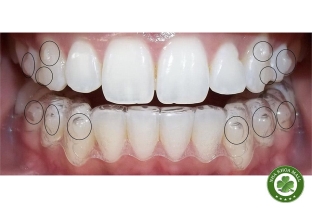

• Chỉnh nha: Niềng răng mắc cài, niềng răng trong suốt, khí cụ chỉnh nha.